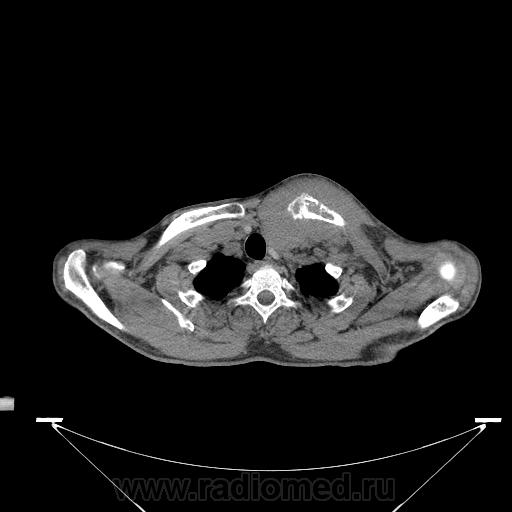

Миелома (плазмоцитома).

Недавний случай. Подтвержден гистологически.  По сцинтиграфии дополнительные очаги гиперфиксации РФП с некоторых ребрах и крестцово-подвздошных сочленениях.